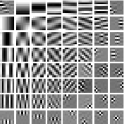

IV-A Transform Learning

To better understand the potential of the MRST model, we vary the number of layers and pre-learn transforms for ST, MRST2, MRST3, MRST5, and MRST7, which possess , , , , and layers, respectively. We used 7 slices of the Mayo Clinic data to train the models. For each model, we run 1000 to 2000 iterations of the learning algorithm to ensure convergence. Fig. 1 shows some of the learned transforms, with each transform matrix row displayed as a square patch for simplicity. The single layer transform displays edge-like and directional structures that sparsify the image. However, with more layers, finer level features are learned to sparsify transform domain residuals in deeper layers. Nonetheless, transforms in deep layers could be more easily contaminated with noise in the training data, since the main image features are successively filtered out over layers.